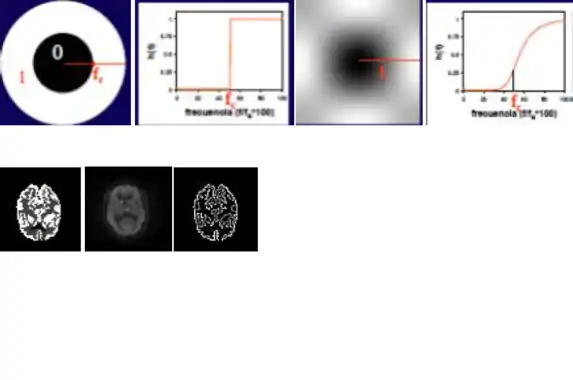

El filtrado las imágenes médicas, en este caso las imágenes de medicina nuclear, pueden asemejar a los filtros paso de banda, debido al estudio de las imágenes en el espacio de las frecuencias (espacio de Fourier).

Los cambios bruscos de intensidad y los detalles finos van asociados a componentes de alta frecuencia, de modo que si se eliminan estos componentes, la imagen resultante que se obtiene a partir de la transformada de Fourier inversa carece de estos detalles finos.

Filtros paso-baja

Este filtro efectúa un filtrado paso-baja cuyo grado de filtrado se controla por el radio del círculo. Un filtro muy abrupto puede producir oscilaciones en la imagen (fenómeno de Gibbs) por lo que suelen emplearse filtros paso-baja como el indicado a la derecha, que tienen una variación más suave. Son filtros con valores altos en el origen y que se atenúan hacia altas frecuencias.

El radio del círculo, que determina el grado de filtrado, se expresa como fracción de la frecuencia de Nysquist.

Filtro paso-alta

La implementación de un filtro paso-alta puede realizarse en el espacio de Fourier, con un planteamiento complementario al del filtro paso-baja.

El efecto de este filtro, que actúa por multiplicación en el espacio de Fourier será, pues, de potenciación de la alta frecuencia y eliminación de la baja frecuencia. Son filtros de realce o de extracción de contornos.

Un ejemplo de filtro paso de alta es el filtro laplaciano, el cual es omnidireccional y extrae contornos en todas direcciones.

Con este tipo de filtros, la detección del contorno es perfecta en las imágenes sintéticas sin ruido, pero en la imagen con ruido del estudio real, el filtro no sólo no detecta el contorno sino que potencia el ruido. Este refuerzo del ruido es una característica de los filtros paso-alta.

El grado de filtrado se controla con el radio del círculo interior, que controla la frecuencia de corte.